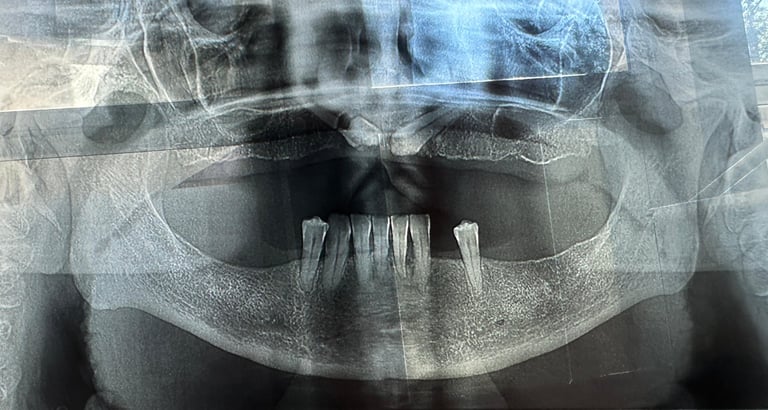

Se deceleaza imagistic o formatiune tumorala radiotransparenta, de mari dimensiuni, localizata la nivelul intregului grup frontal mandibular.

Dupa examenul clinic si imagistic se pune diagnosticul prezumtiv de formatiune tumorala chistica (chist radicular de mari dimensiuni). Se intervine chirurgical realizandu-se extractiile dintilor cauzali, irecuperabili, rezectii apicale a dintilor implicati chistic, care au fost tratati endodontic in prealabil. Piesa operatorie a fost trimisa catre examenul histopatologic, diagnosticul fiind chist radicular fara atipii.